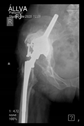

The radiological examination allowed us to verify the close bone-to-implant contact and the unchanged position of the implant during follow-up.

In all the cases operated with the above-described targeting procedure, the stems of the cups remained between the cortical bone surfaces without perforation of the linea terminalis, as shown by postoperative radiographs. There were no complicated surgical situations. In 16 cases, the wound healings were uneventful, and the hips were able to bear weight again after postoperative rehabilitation.